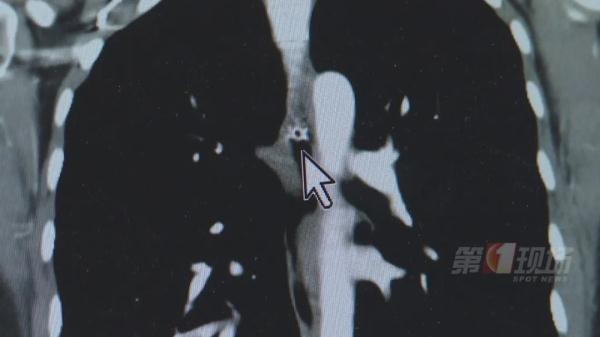

在去医院的路途中、等候检查时,张女士感觉这卡住的鱼骨不断往下滑,从喉咙到锁骨,再到胸部。CT检查确认,一团鱼骨就卡在胸腔的位置,情况较为凶险。

术前片子显示,这团鱼骨卡在食管的中段,与临近的主动脉距离仅仅3.5毫米,而且鱼骨形状非常尖锐。